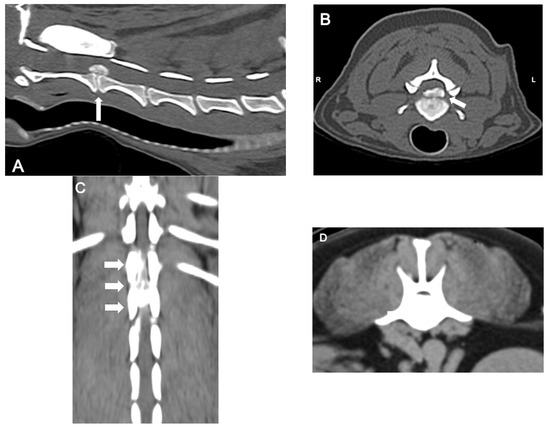

CT (Figure 4) is a rapid and lower-cost diagnostic tool compared to MRI. It offers a sensitivity of 81% to 100%, particularly in chondrodystrophic dogs with mineralized discs. Typical features of disc extrusion seen on CT include hyperattenuating material within the vertebral canal, loss of epidural fat, and distortion of the spinal cord. CT allows for distinguishing between acute and chronic mineralized disc material based on differences in radiodensity and morphology: acute extrusions typically appear as well-defined, dense, and homogeneous structures, while chronic material tends to be fragmented, irregular, or mixed with fibrous tissue. However, CT is reported to be less accurate in older dogs (>5 years) due to age-related disc mineralization that may occur without clinical signs, as well as in small dogs (<7 kg) because of lower spatial resolution and anatomical limitations that reduce contrast and image clarity; moreover, it does not provide details on the severity of intramedullary lesions, limiting its prognostic utility [38,42].

Figure 4.

Computed tomographic (CT) images showing several examples of the appearance of mineralized intervertebral disc extrusion in the vertebral canal. (A) Sagittal reconstructed non-contrast CT image showing a hyperattenuating mass suggestive of extruded disc material into the vertebral canal between C2-3 (arrow). (B) Transverse non-contrast CT image of the same patient showing a large hyperattenuating mass extending into the vertebral canal at the intervertebral disc C2-3 with a mild lateralization to the left (arrow). (C) Dorsal reconstructed post-contrast CT image showing an extensive heterogeneously hyperattenuating material (compared to the spinal cord), suggestive of an extruded degenerated disc mixed with epidural hemorrhage, compressing the spinal cord along the vertebral bodies of T13 and L1. (D) Transverse non-contrast CT image showing a large hyperattenuating mass disc extrusion occupying most of the vertebral canal at the intervertebral disc L1-L2.